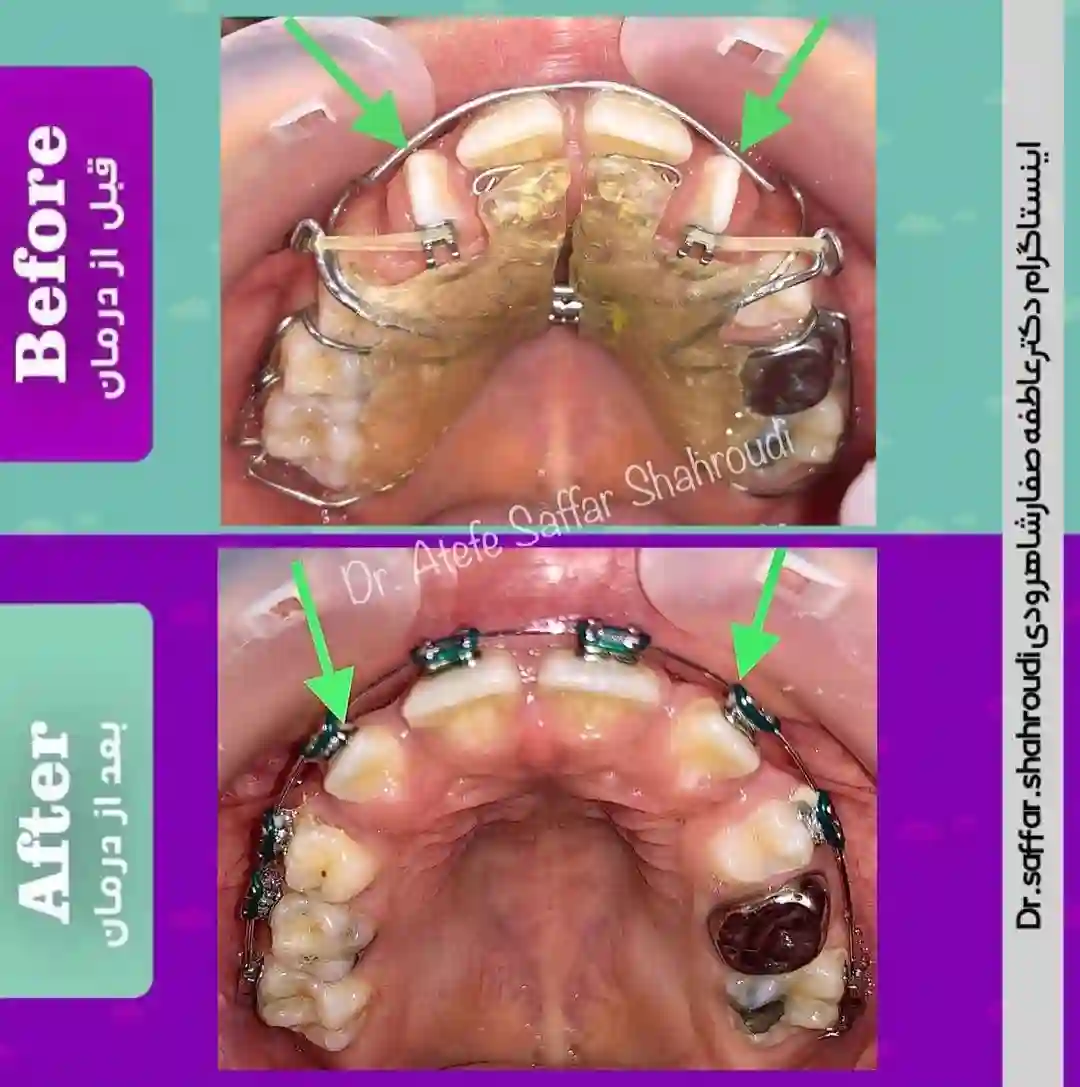

متخصص ارتودنسی (دکتر عاطفه صفار شاهرودی)

ارائه انواع درمان در مرکز تخصصی ارتودنسی دکتر عاطفه صفار شاهرودی . متخصص ارتودنسی و درمان ناهنجاری های فکی. هیئت علمی دانشگاه علوم پزشکی تهران. رتبه برتر آزمون بورد تخصصی . فارغ التحصیل از دانشکده دندانپزشکی دانشگاه تهران.